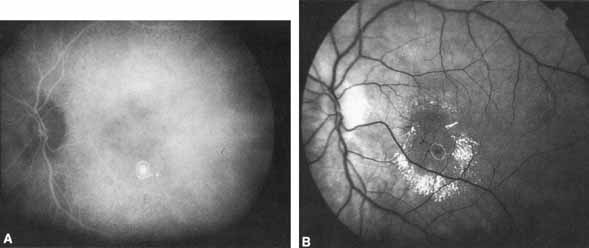

PATHOPHYSIOLOGY OF CHOROIDAL NEOVASCULARIZATION In AMD, it has long been postulated that focal choroidal ischemia may play a role in the development of CNV. Macular choroidal vascular “watershed” zones have been known to exist, but their causal relationship to CNV has never been determined. On ICG angiography, these presumed watershed zones appear as areas of relative, abnormal hypofluorescence in the early phases of the angiographic study.44 A published ICGA analysis by Ross et al.45 revealed a much higher incidence of the presumed watershed zones in the macula of eyes with AMD compared with age-matched control eyes (55% vs. 15%, respectively). Furthermore, Goldberg et al.46 found that 92% of eyes that developed choroidal neovascular membranes had watershed zones. These data support the notion that watershed zones play a role in CNV development and that ICG angiography may be useful once again in identifying eyes at the highest risk for the exudative transformation. Other studies have shown that ICGA can distinguish the different types of drusen and, therefore, may be useful to evaluate the risk of progression of AMD.47 CLASSIC CHOROIDAL NEOVASCULARIZATION Classic CNV as determined by FA shows a similar appearance on ICGA with well-defined hyperfluorescence throughout the transit phase and leakage obscuring the borders of the lesion in the late frames. However, the leakage in the late frames tends to be less pronounced with ICGA. Overall, ICGA offers no advantage over fluorescein angiography in this setting. OCCULT CHOROIDAL NEOVASCULARIZATION Occult CNV assumes a variety of FA patterns.48 There can be obscuration of the neovascularization from fluorescein blockage by overlying fluid or pigment or from rapid leakage of the dye in the area of interest. Sometimes there is slow, irregular fluorescein leakage with poorly delineated borders. With occult CNV, there may be varying degrees of uncertainty as to the precise location and extent of the choroidal neovascular membrane using FA alone. Both fluorescein and ICG dyes appear to be retained by CNV and will, therefore, exhibit hyperfluorescence relative to surrounding tissue.1 ICGA theoretically provides enhanced visualization of CNV in this setting because the ICG infrared fluorescence better penetrates pigment and fluid than the visible light fluorescence of sodium fluorescein, and the highly protein-bound ICG dye leaks less from abnormal vessels compared with fluorescein dye as described earlier. Several patterns of ICG hyperfluorescence for occult CNV have been observed.4,11,49,50 These include early-appearing small hyperfluorescent spots (hot spots), plaque-like hyperfluorescence, collections of abnormal vessels, and late-appearing hyperfluorescence with indistinct edges (Figs. 3, 4, and 5). A combination of these patterns can be seen. Although thin blood is easily penetrated by the infrared fluorescence (Fig. 6), thick blood will still obscure the underlying choroidal pattern to some degree. Reichel et al.51 demonstrated that ICGA was superior to fluorescein angiography in determining the extent of CNV secondary to age-related macular degeneration obscured by hemorrhage. Several investigators have demonstrated the ability of digital ICG angiography to not only confirm, but also better delineate CNV in certain cases of exudative AMD.1,3,4,10–13,33 Early large series by Yannuzzi et al.4,52 and Regillo et al.,11 using digital videoangiogram systems demonstrated well-defined hyperfluorescent foci of ICG presumably corresponding to the entire choroidal neovascular process in approximately 40% of cases, where FA revealed occult or ill-defined CNV only (see Figs. 3, 4, 5, and 6). A similar yield was reported early on by Kuck et al.,13 using SLO-based ICGA. Furthermore, studies by Regillo et al.,11 Sorenson et al.,53 and Guyer et al.54 have shown that laser photocoagulation of well-defined ICG hyperfluorescent foci with treatment guided solely by the ICGA findings resulted in short-term resolution of exudation and stabilization or improvement of vision in 56% to 69% of cases. Although prior studies with AMD patients have shown that occult or ill-defined CNV on FA have, in general, a poor visual prognosis,55,56 adequate controls are not available to determine whether laser therapy as outlined in these studies significantly altered the natural history. Nonetheless, the data suggest that treatment based on ICGA findings may result in prompt resolution of exudation and improved visual acuity in selected cases. Therefore, this technique has the potential to increase the yield of exudative AMD cases that may be effectively managed by conventional laser photocoagulation treatment methods. SERIOUS PIGMENT EPITHELIAL DETACHMENTS In contrast to the bright hyperfluorescence on FA, serous pigment epithelial detachments most often appear either isofluorescent or slightly hypofluorescent; associated hyperfluorescent CNV is, therefore, more easily seen on ICGA (Fig. 7). In AMD, a serous pigment epithelial detachment (SPED) is usually associated with CNV. However, the CNV may not be adequately visualized with fluorescein angiography because of rapid fluorescein pooling into the sub-pigment epithelial space. With ICGA, the neovascular component shows a relative hyperfluorescence, whereas the serous component of the complex is isofluorescent or hypofluorescent due to the minimal amount of ICG leakage(Fig. 7) It was initially hoped that this would lead to an increased yield of successful laser treatment of such lesions. Baumal et al.57 demonstrated that ICGA revealed CNV associated with SPED in 83% of eyes in which the CNV was not well delineated by fluorescein angiography. However, laser treatment to the presumed neovascular focus as guided by the ICGA findings did not change the visual outcome compared to controls. Lim et al.58 showed a transient stabilization of visual acuity following ICGA-guided laser photocoagulation for CNV associated with SPED. However, the treatment benefit diminished with time. The collective experience of Retina Service members at Wills Eye Hospital indicate that most eyes with SPED do not seem to benefit from treatment, although there are occasional dramatic, favorable results. This is especially true if the neovascularization on ICG angiography is small and located at the edge (rather than within) of the SPED.44 PRE– AND POST–LASER TREATMENT ICGA may be a useful adjunct to FA in determining the presence or extent of recurrent CNV.4,11,53 Photocoagulated areas on ICGA are completely hypofluorescent, and, compared with FA, there is greater contrast between the photocoagulated site and any associated persistent or recurrent CNV (Fig. 8). Preliminary data reveal a good correlation between treatment success and the lack of any residual abnormal ICG hyperfluorescence, indicating that the ICGA may accurately identify the presence of CNV.11,53 This is further supported by a human clinicohistopathologic study in which a well-delineated plaque of hyperfluorescence on the ICGA corresponded precisely with abnormal subretinal pigment epithelial fibrovascular tissue identified by histopathologic examination of serial sections.59 Regillo et al.60 evaluated persistent and recurrent choroidal neovascularization and found ICGA to improve visualization of ill-defined choroidal neovascular complexes seen on fluorescein angiography. However, ICGA was not useful when evaluating post-treatment fluorescein angiograms negative for any CNV or when the FA showed well-defined CNV. ATYPICAL NEOVASCULAR MACULAR DEGENERATIONS Idiopathic Polypoidal Choroidal Vasculopathy Polypoidal choroidal vasculopathy is a form of CNV with recurrent subretinal and sub-RPE serosangiousmacular detachments. The condition originally was thought to occur mainly in African-American women ages 40 to 80 years who are hypertensive or diabetic.61 However, recent studies have found this condition in Caucasian and Asian patients.62 IPCV demonstrates branching inner choroidal vessels with terminal aneurysmal-like dilatations. These lesions are most commonly found in the peripapillary region. However, isolated lesions can also be found in the macula or peripheral fundus.63IPCV appears as early, intense unilateral or multifocal hyperfluorescent “hot spots” on ICGA. The late phase of the ICGA shows a washout from the center of the polypoidal lesion with staining of the surrounding choroidal vasculature64–70 (Fig. 9) We have used ICGA to aid in the diagnosis of a case of presumed idiopathic polypoidal choroidal vasculopathy.64,65 The characteristic multiple, saccular aneurysmal-like dilatations in the choroid were readily apparent under associated blood and exudate (Fig. 12). Conventional thermal laser photocoagulation of these choroidal vascular anomalies can lead to resolution of the exudative manifestations, and the ICGA may serve to guide treatment analogous to localizing and directing laser treatment in selected cases of exudative macular degeneration.63 Successful treatment of IPCV lesions with photodynamic therapy has also been described.71 Retinal Angiomatous Proliferation Retinal angiomatous proliferation (RAP) is a form of neovascular AMD in which the neovascularization appears to originate in the inner retinal layers then extends into the subretinal space, sometimes leading to a retinal-choroidal anastomosis. RAP lesions have a well-defined retinal–retinal anastomosis between the normal retinal vasculature and deep retinal vascular complex. With conventional fundus-camera based ICGA, RAP lesions show intense focal hyperfluorescence (hot spot) corresponding to the intraretinal neovascular focus. The lesion becomes more hyperfluorescent in the mid and late phases of the ICG as the dye leaks intraretinally.72 With SLO-based ICGA, both retinal feeding and draining vessels are often readily identified. RAP lesions are most easily detected when associated with a SPED with a background of ICGA hypofluorescence (Fig. 10) Identification of early stage RAP lesions may allow for successful treatment by a variety of approaches, such as conventional thermal laser treatment, photodynamic treatment (PDT), or surgical ablation of the anastomotic retinal vessels.73,74 Choroidal Feeder Vessel Treatment Using SLO-based ICGA, investigators have been able to identify choroidal “feeder” vessels of AMD-related subfoveal choroidal neovascularization. The SLO allows for rapid image acquisition with rates of up to 20 frames per second. This allows for differentiating choroidal arteries from veins, which is not possible with fundus camera-based ICGA. Using SLO–ICGA and concentrating on the early choroidal filling phase, investigators have been able to identify choroidal vessels that directly feed CNV in selected cases (Fig. 11) Treatment of these “feeder” vessels with laser photocoagulation may or may not result in long-term involution of CNV.75–79 Further study with this treatment approach is needed. MISCELLANEOUS MACULAR DEGENERATION STUDIES Studies have suggested that ICGA may have predictive value for the development of CNV in AMD. Different groups of investigators have found that eyes known to have dry AMD with only drusen and alterations in the retinal pigment epithelium and no leakage on fluorescein angiography occasionally harbor ICG hyperfluorescent plaques. The plaques were discovered incidentally in patients in whom the fellow eyes had active exudative signs. By following these patients over time, it was determined that the eyes that were clinically dry with ICG hyperfluorescent plaques were much more likely to develop exudative manifestations than dry AMD eyes without ICG abnormalities.80,81 Therefore, in people with dry AMD in one eye and a history of CNV in the fellow eye, the presence of incidental, abnormal ICG hyperfluorescence in the “dry” eye may be a predictive indicator of future exudative changes in that eye.44 |